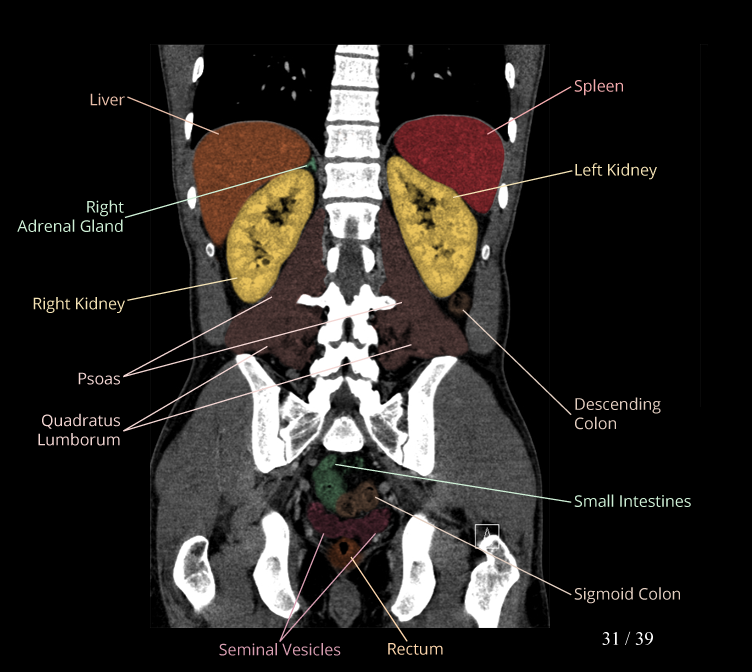

Body

Covers abdominal CT anatomy.